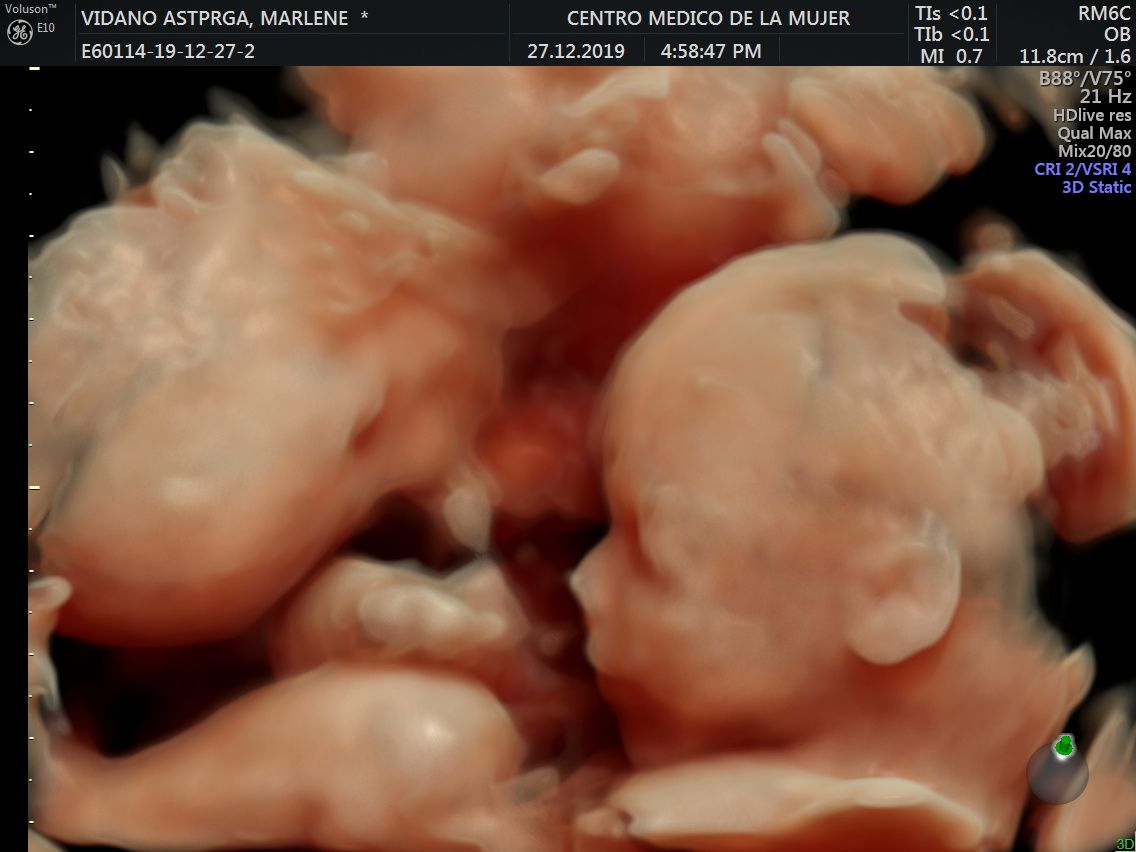

Fotos y videos

ECO Anatómico

Consiste en la evaluación especifica de cada organo y sistema del bebé con medidas detalladas de cada parte para evaluar su crecimiento proporcional.